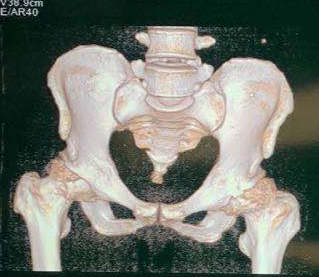

圖二

李寬新主任接診后詳細(xì)詢(xún)問(wèn)病史、體格檢查(圖一),結(jié)合患者術(shù)前骨盆平片,骨盆CT(圖二、三)平掃三維重建,診斷為:“雙側(cè)股骨頭壞死繼發(fā)終末期骨關(guān)節(jié)炎(Ficat IV期)”。為實(shí)行快速康復(fù),精準(zhǔn)解剖重建髖關(guān)節(jié),提出應(yīng)用微創(chuàng)OCM入路聯(lián)合Harris窩技術(shù),實(shí)現(xiàn)微創(chuàng)和精準(zhǔn)全髖關(guān)節(jié)置換的治療方案。